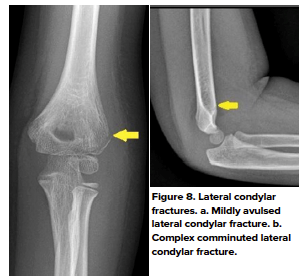

- Lateral condylar fractures

- Lateral condylar fractures are the second most common pediatric elbow fracture, accounting for 10%-15% of elbow fracture, with a peak age of 6-10 years old.9 Patients usually present with lateral elbow pain after a FOOSH with the forearm in supination, creating a varus force on the elbow. A nondisplaced lateral condylar fracture is often very subtle and challenging to detect on conventional radiographs. Joint effusion and soft tissue swelling may provide secondary signs as to the presence of the lateral condylar fracture. (Fig 8 a,b)